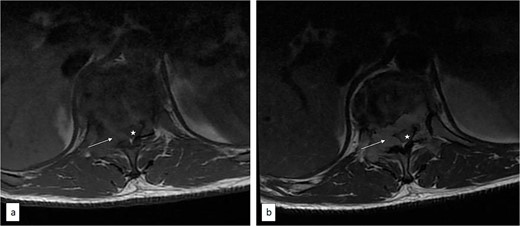

Axial T1 pre (a) and post (b) contrast thoracic spine MRI showing contrast-enhancing extradural tumour (arrow) compressing the spinal cord (asterisk).